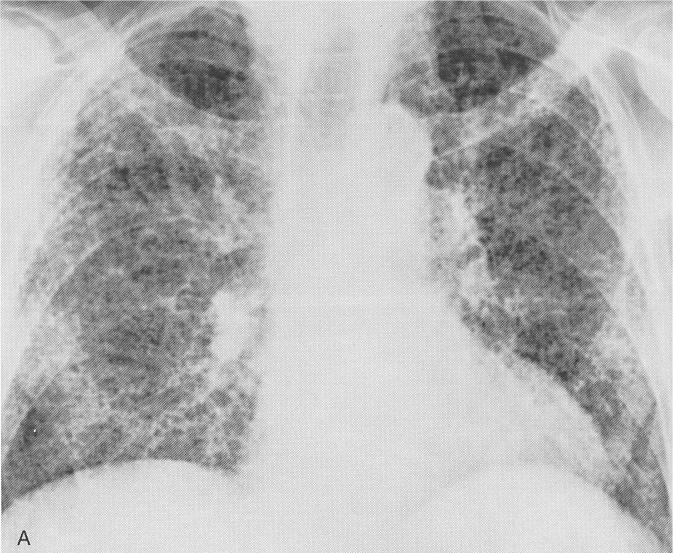

- Fibrosis pulmonar